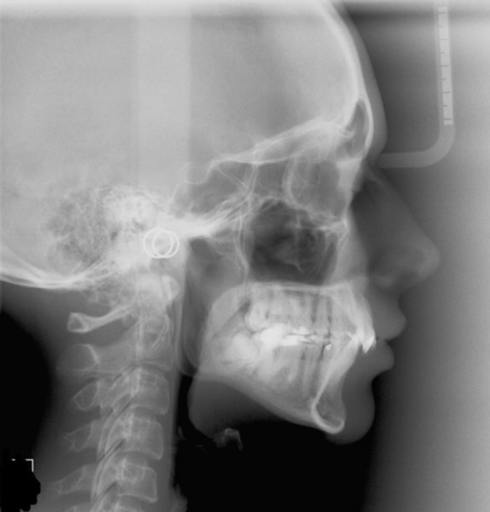

Attached is an image of my condyles. Are they normal and healthy or Do you see any bone loss such as flattening or erosion of them? If there does appear to be some bone loss, how does this affect my bite and the appearance/position of my jaw?? Is there any way to tell how long ago the bone loss occurred or if it is still active? Is there any way to get damaged condyles back to their previous state? (These are all questions I’m curious about the answers to even if my condyles end up appearing that they don’t have bone loss to you). Here is a link to a second image since it won’t let me upload more than one. https://ibb.co/jEowge

Attached is an image of my condyles. Are they normal and healthy or Do you see any bone loss such as flattening or erosion of them? If there does appear to be some bone loss, how does this affect my bite and the appearance/position of my jaw?? Is...